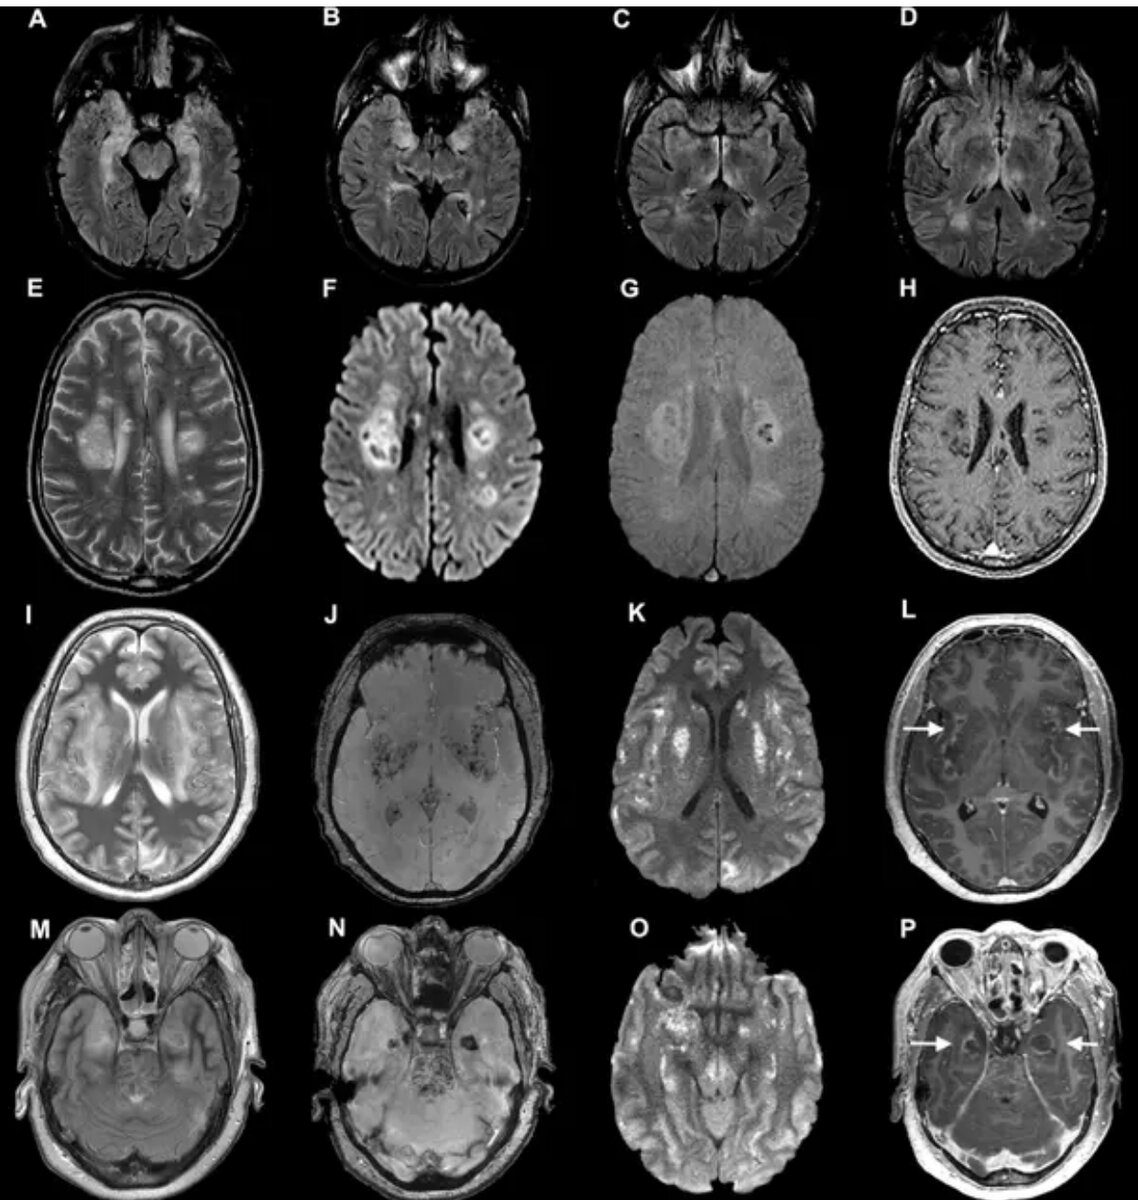

Сканирование мозга пациентов с коронавирусом из исследования, опубликованного в июле. Ученые обнаружили, что у некоторых развиваются серьезные неврологические осложнения, включая повреждение нервов.Кредит ...Росс У. Патерсон, Рэйчел Л. Браун и др. / Брейн, Oxford University Press